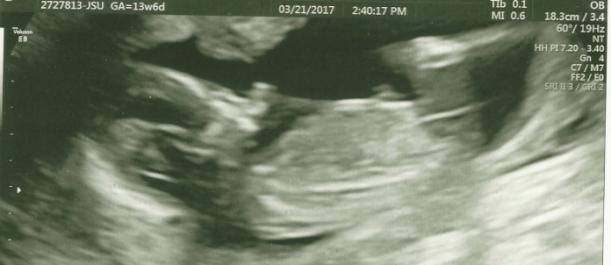

Can't tell if this is a boy nub or a girl because of the strong line?Attachment 35495

I'd say girl, yeah x

Girl [emoji175]